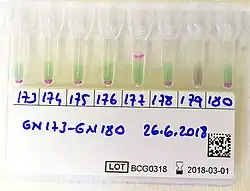

Livestock vaccination and disease surveillance

Vaccination is the most effective method for controlling brucellosis in livestock. In cattle, the most common vaccines are Brucella abortus strain 19 and RB51,[26] while for goats and sheep, B. melitensis Rev-1 is used. Other methods include regular serological screening, and the culling of infected animals helps prevent the spread of disease. In many countries, mandatory vaccination programs[27] and test-and-slaughter policies have been shown to significantly reduce brucellosis incidence in livestock populations.[28][29]